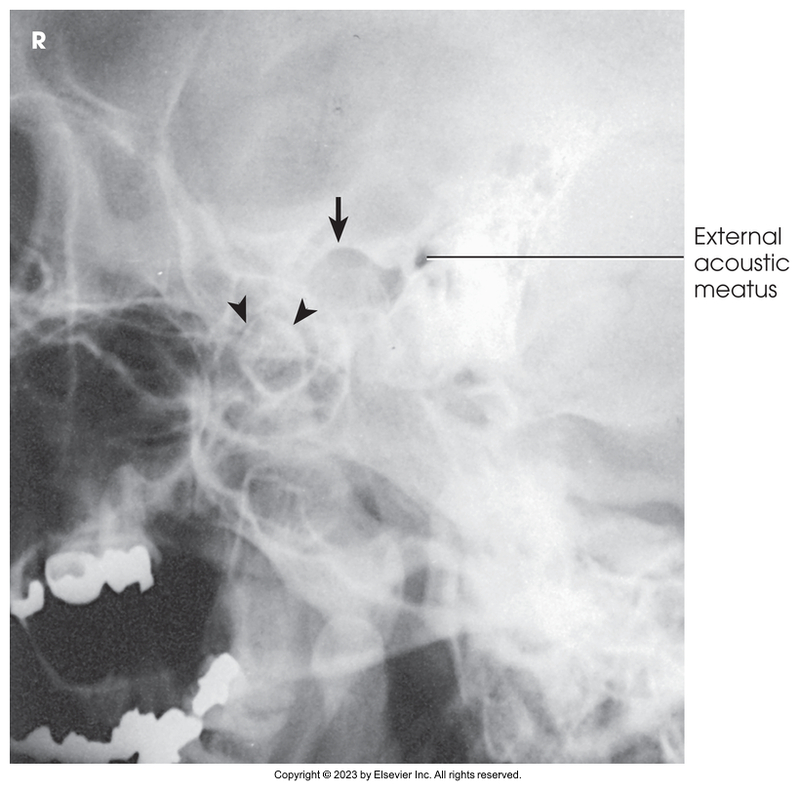

Axiolateral of TMJs - Modified Schuller Method (closed mouth)

Axiolateral of TMJs - Modified Schuller Method (open mouth)

Axiolateral of temporomandibular joint - Modified Schuller method (mouth closed)

Axiolateral of temporomandibular joint - Modified Schuller method (mouth opened)